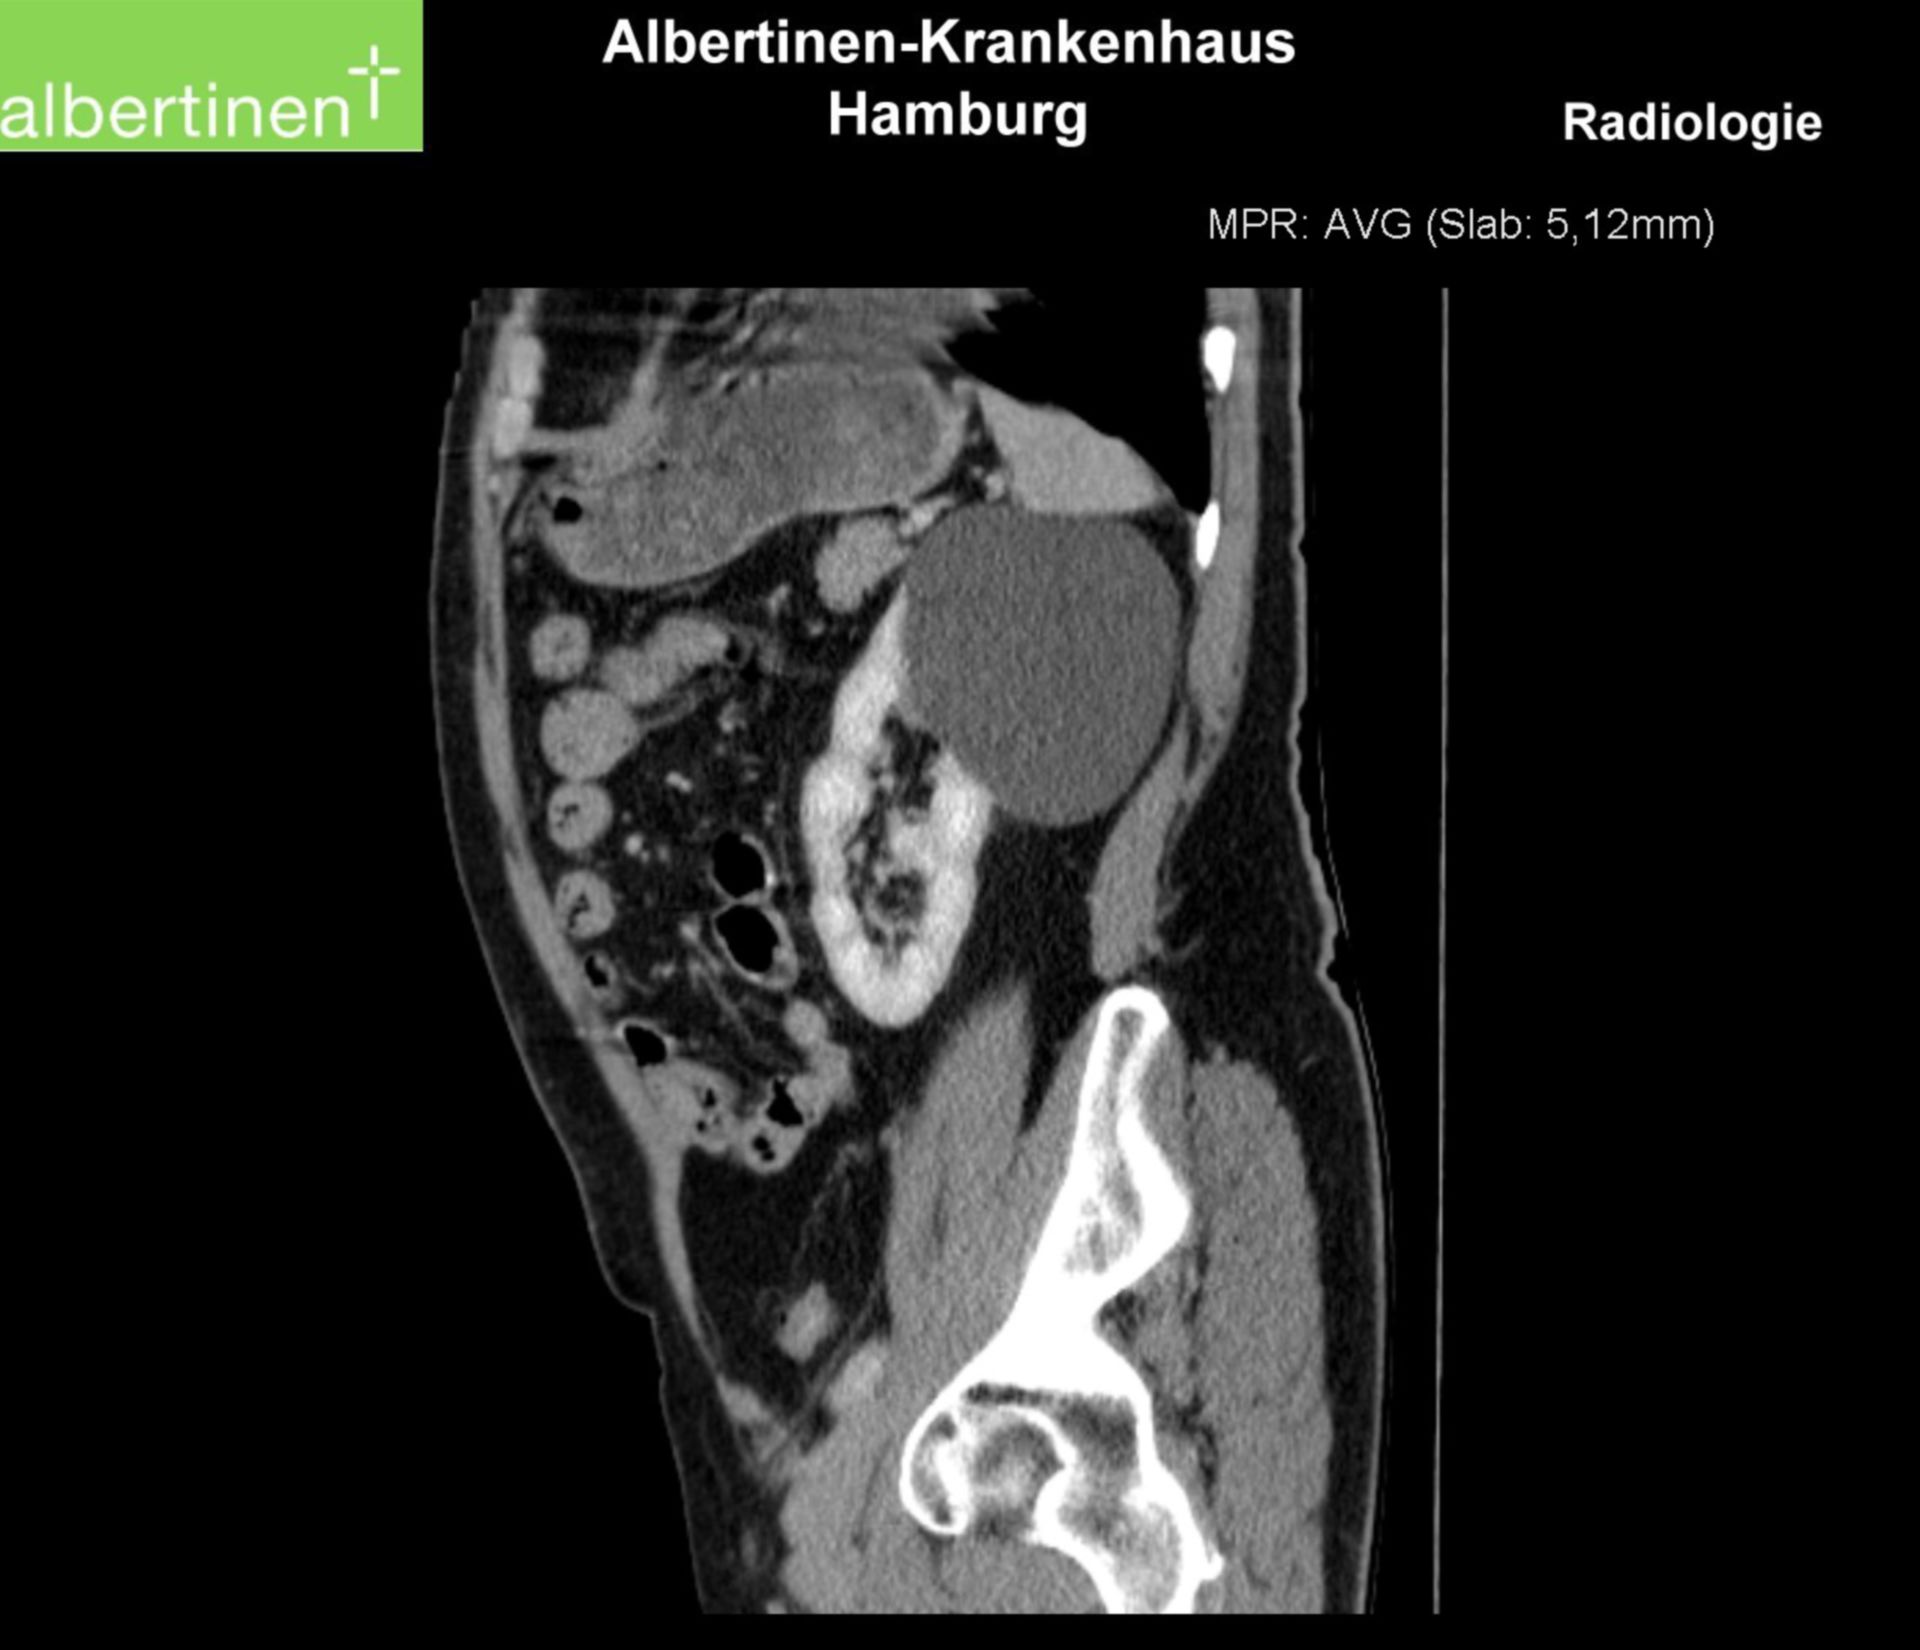

Große "Rucksackzyste" an der linken Niere, kleine Zyste rechts (CT Abdomen mit Kontrastmittel, coronare Rekonstruktion).